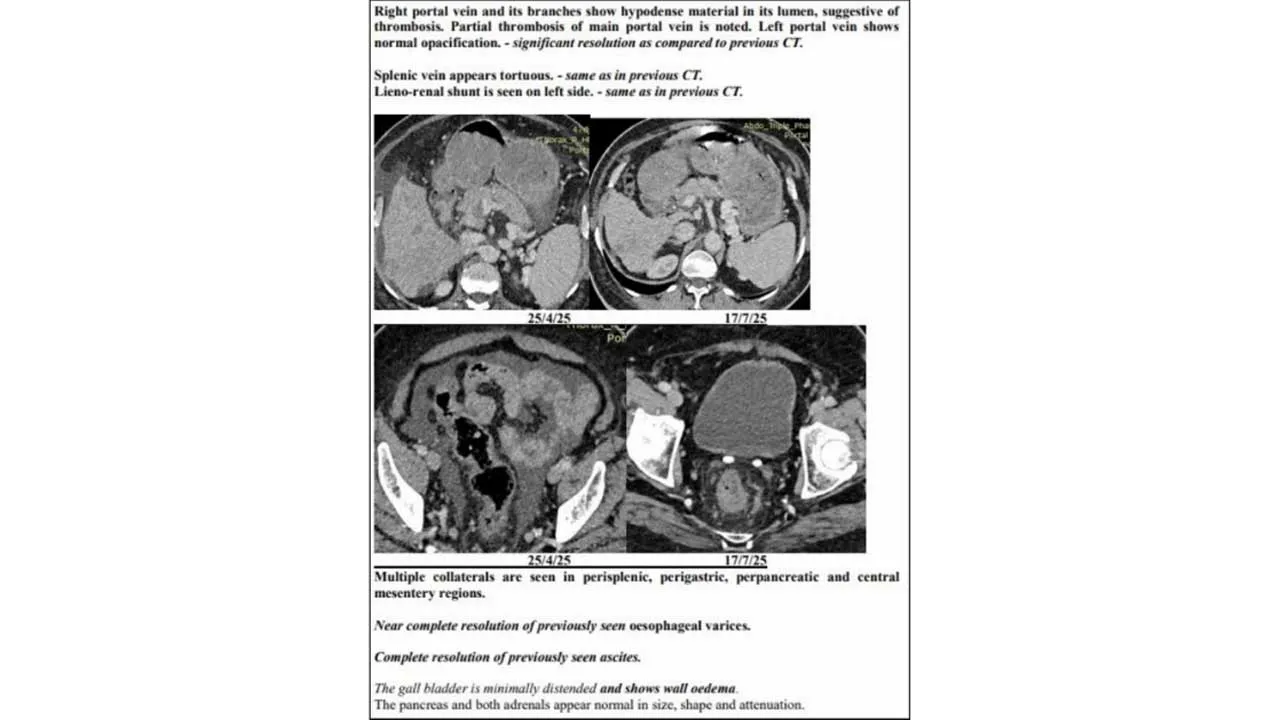

પરંતુ માત્ર ત્રણ મહિનામાં, જુલાઈની બપોરે, પરિવારએ બીજો સ્કેન જોયો – ટ્યુમર ઘટીને એક જ પેચમાં સીમિત, નસોમાં ફરીથી લોહી વહેવાનું શરૂ, પાણીનો ભરાવો ગાયબ. ટ્યુમર માર્કર 1,000 ng/mLથી ઘટીને 10 પર આવી ગયો. પરિવાર માટે આ ચોંકાવનારો વળાંક હતો.

જુલાઈના સિટી સ્કેનમાં સાબિત થયું – ટ્યુમર ઘટીને નાના થયા, પેટનું પાણી ખતમ, તમામ આંકડા નોર્મલ. એક વરિષ્ઠ રેડિયોલોજિસ્ટે જણાવ્યું: “આવી રિવર્સલ એડવાન્સ લિવર કેન્સરમાં અતિશય દુર્લભ છે. લગભગ અવિશ્વસનીય.”